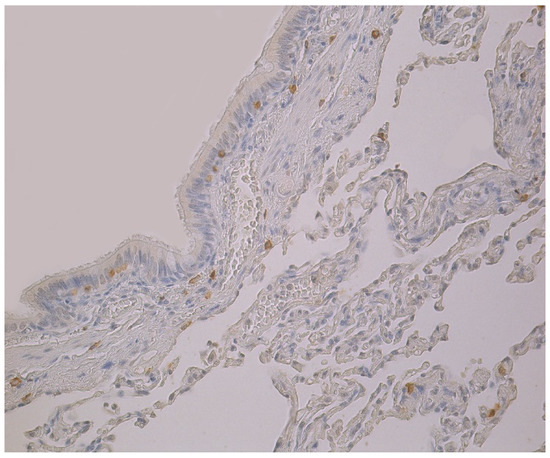

3.2. Immunohistochemical (IMH) Data